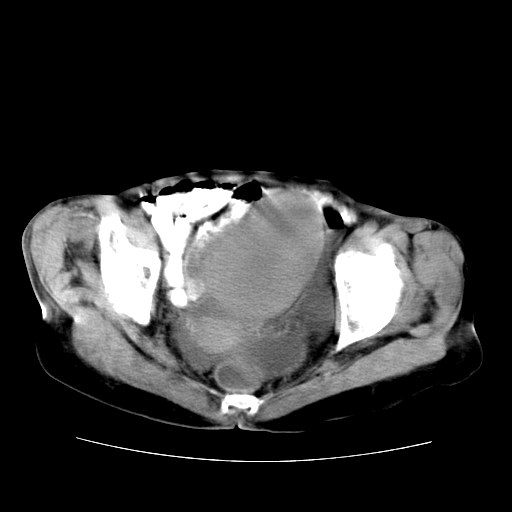

女性,72岁。

主诉下腹部坠痛不适1年余。

子宫增大如孕3月大小,质软,活动可,无压痛。

b超提示:盆腔(子宫前方)低回声团块。

临床诊断:盆腔肿块查。

1、这个肿瘤密度均匀,增强后轻中度均匀性强化,与左侧附件关系密切,肿瘤边缘光整、清晰。

2、左侧卵巢增大呈8×8×10cm大小,实性,表面光滑,边清,左侧输卵管爬行于左卵巢上,子宫萎缩。右输卵管、卵巢萎缩。

3、病理号:092658

左侧卵巢纤维瘤(性索间质肿瘤)

卵巢纤维瘤为良性卵巢性索间质肿瘤,常为单侧发病,当合并腹水或胸腹水时称麦格斯(meigs)综合征,肿瘤切除后胸腹水可消失。ct表现为盆腔内边界清楚的圆形或椭圆形肿块,常有分叶或不规则;肿瘤多为实性,少数为囊性、囊实性,完全囊性者可见壁结节。实性部分与子宫等密度;增强扫描常为轻度强化或几乎不强化。